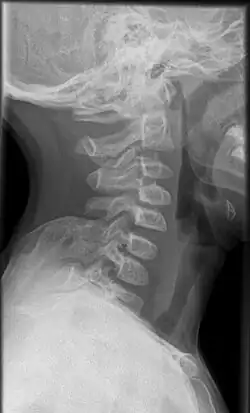

Häufig findet sich neben einer Verkürzung der Halsmuskulatur ein bindegewebiger oder knorpeliger Strang zwischen oberem Skapularand und Wirbelanhangsgebilden der unteren Halswirbelsäule. Ist dieser knöchern ausgeprägt, wird er als Omovertebralknochen, Os omo-vertebrale, bezeichnet und ist auf Röntgenaufnahmen erkennbar. In den anderen Fällen kann dieser Strang im Kernspintomogramm (MRT) dargestellt werden.